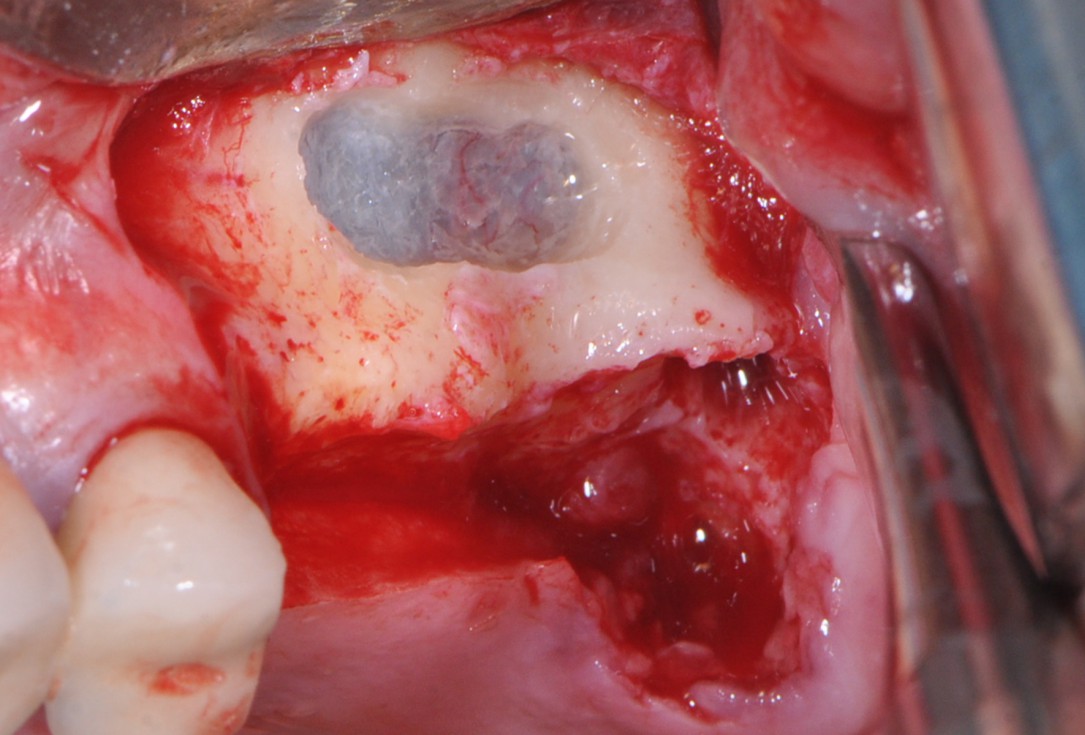

5/16 - Schneiderian membrane perforation

One-stage sinus lift - Dr. V. Kalenchuk

6/16 - collprotect® membrane protecting Schneiderian membrane

One-stage sinus lift - Dr. V. Kalenchuk